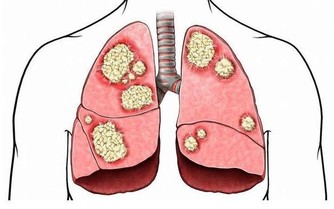

在過去的30年,我國肺癌死亡率上升了465%,

肺癌已經成為我國惡性腫瘤的第一位死亡原因,嚴重威脅大眾健康。

據統計,近50多年來,世界各國特別是工業發達國家,肺癌的發病率和病死率均迅速上升,

目前是全世界癌症死因的第一名,成為名副其實的“頭號殺手”。

肺癌的典型症狀是咳嗽、痰中帶血、胸痛等肺部表現,但是,約有半數肺癌患者一開始表現出在肺外的症狀。